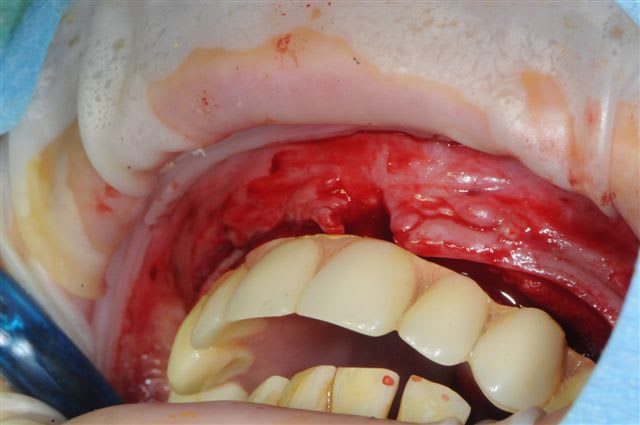

je peux enfin confirmer que la greffe biobank, autorise l'expansion en deuxième intention.

même si je n'ai pas fait un super bombé vestibulaire je me suis permis de faire un mini expansion de crête en particulier sur 22

Très joli le résultat de la greffe

os magnifiquement vascularisé! excellente adhérence du greffon.

Concernant la résorption du greffon, même constatations que Growler: aucune, les seuls zones qui ont fait reculer la date d'intervention, de 2 mois sont des zones de jonction avec l'os du patient qui avait du mal à fusionner car trop fin au départ (moins d'un mm)je pense.

l'expansion en 22 à la jonction greffon os propre, faite à l'ostéotome manuel, malgré la non approbation de Thomas, c'est parfaitement passée, et nous avons constatés la parfaite liaison du bloc.